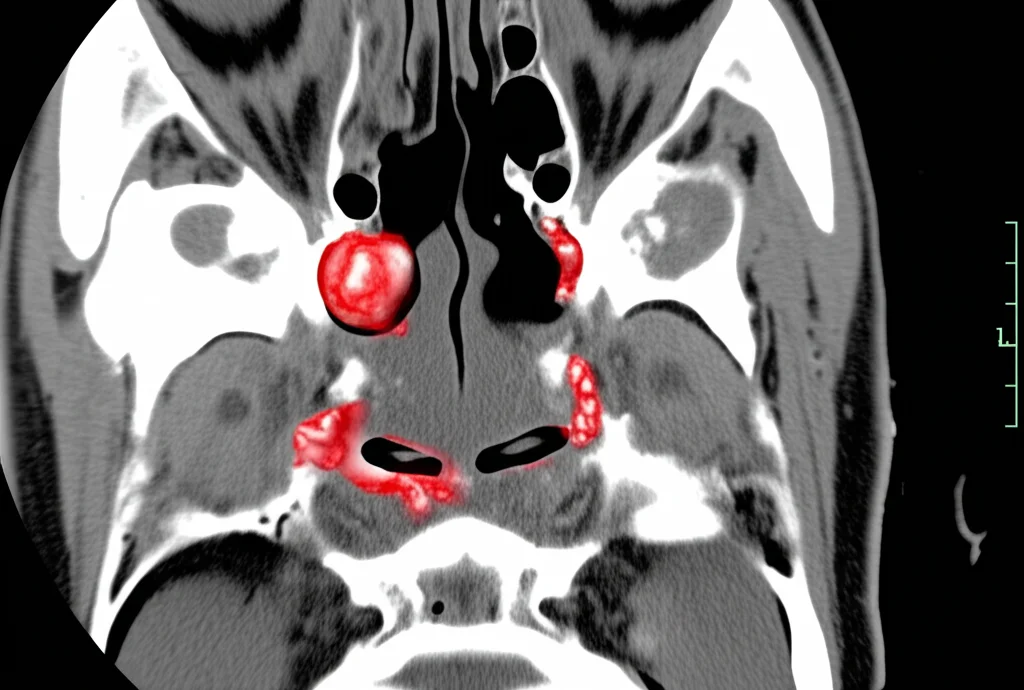

Reperti alla TAC dei Seni Paranasali

Qui le anomalie erano frequentissime, presenti nell’84,5% dei pazienti esaminati. Le più comuni:

- Presenza di tessuto molle nei seni (41,5%): Spesso indice di infiammazione cronica della mucosa (rinosinusite).

- Poliposi nasale (34,0%): Crescite benigne all’interno delle cavità nasali e dei seni, fortemente associate a certi tipi di asma.

- L’asma eosinofilico era significativamente associato a ispessimento delle pareti bronchiali e opacità a vetro smerigliato alla TAC toracica, e a poliposi nasale alla TAC dei seni. Sembra proprio che l’infiammazione eosinofilica lasci un’impronta visibile!

Inoltre, hanno notato che reperti come bronchiectasie e atelettasie lineari alla TAC erano più comuni nei pazienti più anziani, con asma da più tempo e con FEV1 più basso, suggerendo che il carico cronico della malattia possa portare a danni permanenti. E, come ci si poteva aspettare, la presenza di tessuto molle e polipi nei seni paranasali era fortemente legata alla coesistenza di rinosinusite cronica e alla sindrome NERD (malattia respiratoria esacerbata da FANS).